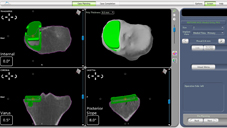

機器人手臂設備

術前三維電腦斷層掃描輸入機器人手臂,以供術前計畫及術中執行所需。